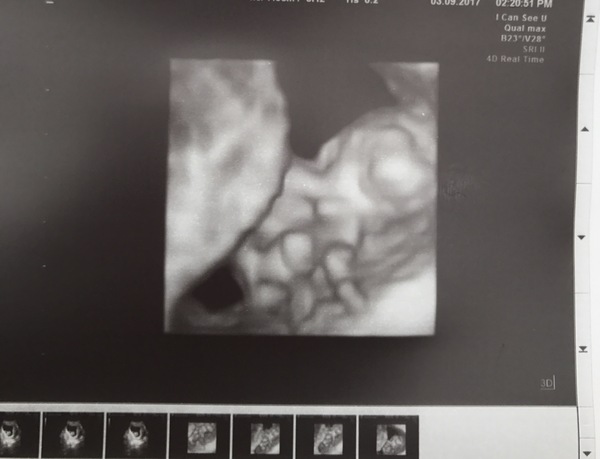

starsshinebright · 03/09/2017 16:00

Scan went well! Managed to see the baby in 4D.

Wow @starsshine I didn't realise they could do 4D scans this early! I'm looking forward to getting on done around the 30 week mark and you can see a little squishy face ☺️